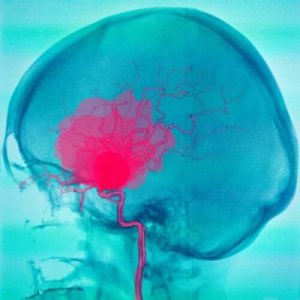

इंसानी ब्रेन में मौजूद तीन मेनिन्जेज में से दो का नाम है ड्यूरा और एरेक्नॉइड। मेनिनज ऐसी संरचनाएं हैं जो सेन्ट्रल नर्वस सिस्टम को ढकती हैं। सबएरेक्नॉइड और सबड्यूरल हेमरिज वह रक्तस्राव है जो इन दोनों हिस्सों में होता है।

सबएरेक्नॉइड हेमरिज में एरेक्नॉइड और पिया मैटर के बीच खून का पूल इकठ्ठा हो जाता है। खून आमतौर पर धमनियों से आता है और इसके कई कारण हो सकते हैं। सबसे आम एन्यूरिज्म (aneurysm) का फटना है। हालाँकि इसके दूसरे कारण भी हो सकते हैं।